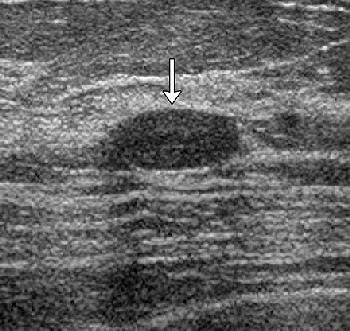

| Transverse images of fibroadenoma obtained in a 35-year-old woman during (a) conventional US and (b) tissue harmonic imaging. (a) A 1.0-cm oval-shaped slightly hypoechoic mass (arrow) is seen. (b) The mass (arrow) appears more hypoechoic and the circumscribed margin is clearly delineated. The final assessment by all readers was "probably benign" at both conventional US and tissue harmonic imaging. |